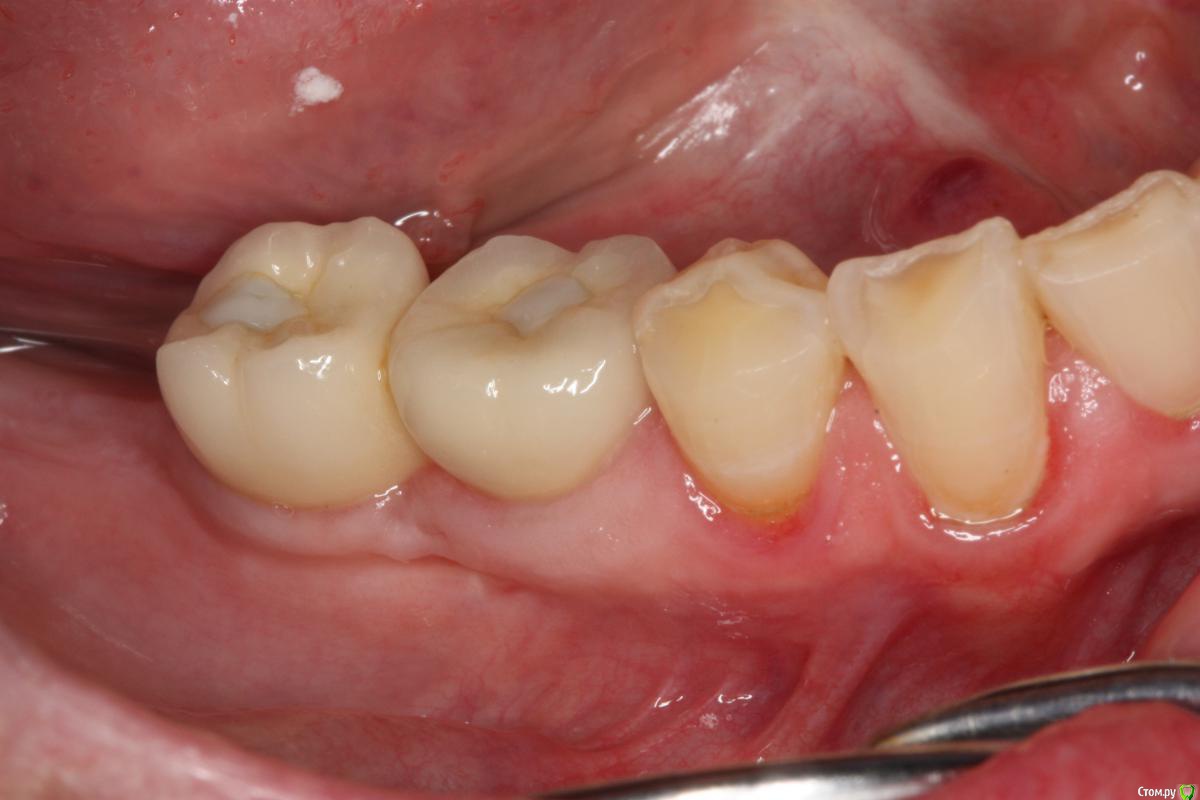

Pavel-Pskov Опубликовано 24 мая, 2016 Поделиться Опубликовано 24 мая, 2016 В момент снятия слепков май 2014 г.Неделя назад Ссылка на комментарий